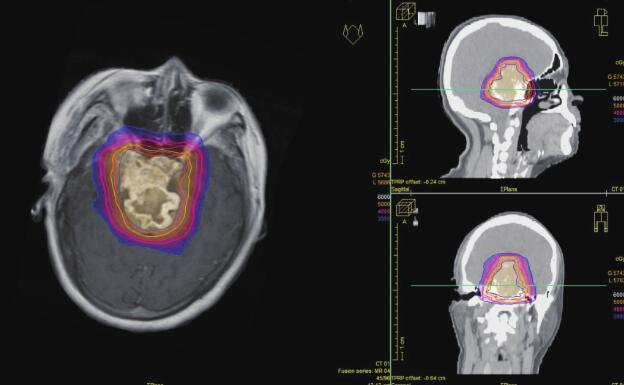

患者术后病理回报:(右中颅底)高分化软骨肉瘤。患者外科病房出院后就诊放疗中心行放疗,予6MV X线局部野IMRT放疗DT:54.75Gy/26Fx(图2),病程中予对症支持治疗。患者放疗前后(图3、图4)病灶缩小。患者随访至2017年8月,病灶稳定,症状同前。

图4 2015-6患者放疗后复查MRI,提示鞍上区病灶较放疗前(图2)略缩小